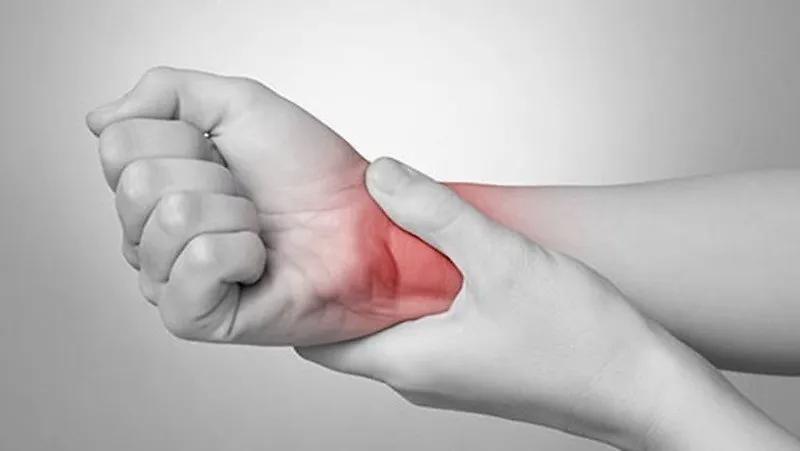

在健身过程中,不管是做有氧运动为主,还是以无氧运动为主,都会或多或少地受到一点伤。在运动过程中学会如何保护好我们的身体,降低受伤几率,至关重要。下面就来介绍一下在健身过程中如何避免腕关节受伤。

一、腕关节急慢性损伤和常见的受伤部位。

腕关节损伤分为急性和慢性损伤,急性损伤表现为腕部疼痛,活动时疼痛加剧,有肿胀和皮下瘀斑,腕关节活动受限,急性损伤大多是突然间受伤,相对较容易之类;慢性损伤疼痛没有急性和强烈,在做幅度较大的动作时疼痛很明显,肿胀不明显,腕部感觉无力、不灵活,慢性损伤大多数由于动作不标准,缺乏热身等原因所致,不仅要治疗疾病,还要纠正动作、做好热身,治疗起来相对较麻烦。

从腕关节受伤的具体部位来说,主要分为大拇指一侧的腕管综合征、桡骨茎突腱鞘炎,小拇指一侧的三角盘软骨损伤三种。